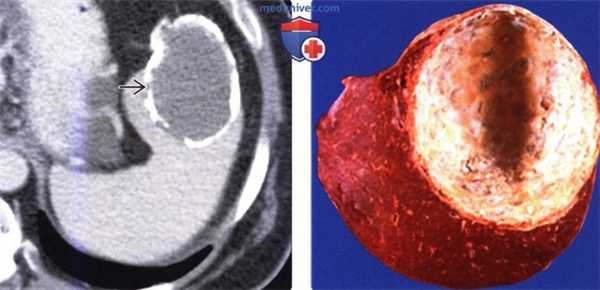

(Слева) На аксиальной КТ с контрастным усилением в селезенке визуализируется объемное образование с обызвествлениями в стенке, имеющее плотность, близкую к плотности воды. Обратите внимание, что мягкотканный компонент, накапливающий контраст, в кисте отсутствует.

(Справа) Макропрепарат удаленной (у этого же пациента) селезенки: кальцинированная стенка кисты, состоящая из фиброзной ткани. Эта киста является приобретенной и возникла, скорее всего, в результате травмы или инфаркта. (Слева) На корональной КТ с контрастным усилением у молодой девушки визуализируется большая киста в селезенке, выглядящая простой. Пациентка предъявляла жалобы на боль и раннее насыщение, ей было выполнена операция — иссечение стенки кисты.

(Справа) Макропрепарат удаленной (у этого же пациента) селезенки: кальцинированная стенка кисты, состоящая из фиброзной ткани. Эта киста является приобретенной и возникла, скорее всего, в результате травмы или инфаркта.